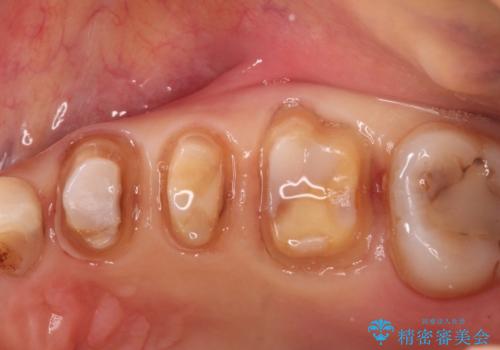

- 定期健診にて虫歯が見つかった患者さんです。県外からお越しいただいている事もあり、かなりお久しぶりの来院でした。歯と歯の間のところと銀歯の下が虫歯になっていました。被せ物はオールセラミッククラウンで治療しました。

銀歯を外すとかなり大きな虫歯になっていました。幸いぎりぎりのところで神経まで虫歯は広がっていなかったため、症状が出ない事を確認した後、オールセラミッククラウンで治療しました。虫歯除去後、残っている歯質が少なかったため、破折抵抗を考慮し部分的な被せ物ではなくクラウンを選択しました。